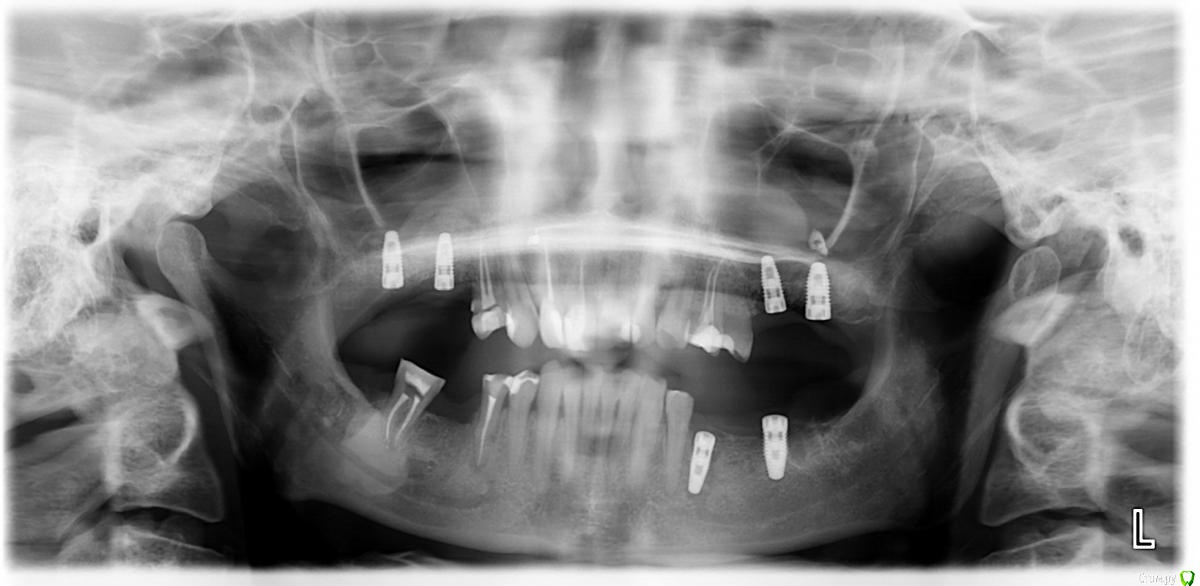

Garotta Опубликовано 25 июня, 2015 Автор Поделиться Опубликовано 25 июня, 2015 Мне казалось, что причин как раз я никаких не называю, я их пытаюсь найти.А ортопантограмму прямо сейчас я выкладываю промежуточную: из представленных имплантов два уже переустановлены, а один на тот момент (который удалили сегодня) еще не был установлен. Ссылка на комментарий

Bier Опубликовано 26 июня, 2015 Поделиться Опубликовано 26 июня, 2015 Спасибо, снимка достаточно. Все ясно. Врача поменяйте. 2 Ссылка на комментарий